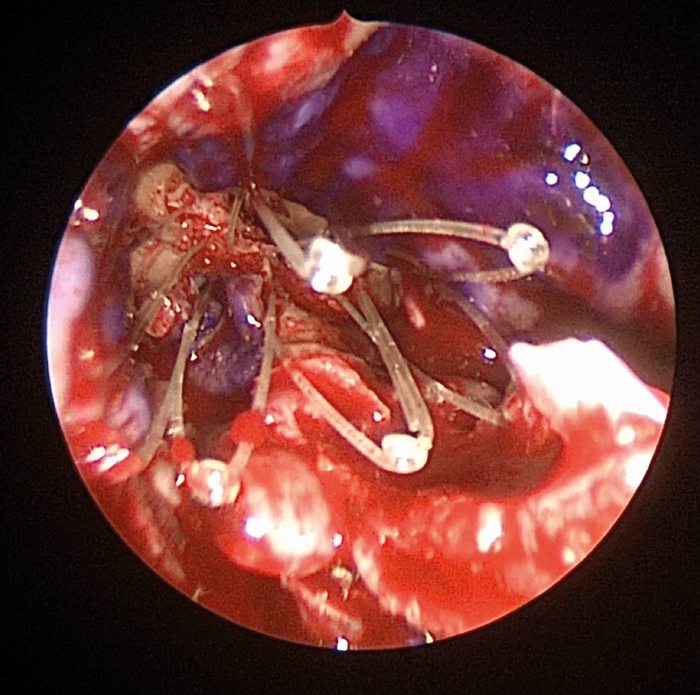

Figure 2. Placement of a Propel* implant in a Draf 3 frontal sinusotomy. An extended midline frontal sinusotomy has been performed and mucosal grafts placed over the exposed bone (mucosal surface of grafts stained with methylene blue). The implant will now be teased out so that it lies in firm contact with the grafts and, as well as eluting mometasone, it will hold the grafts in place. (* IntersectENT, Menlo Park, CA).

Such implants may also obviate one concern regarding balloon technologies in the future - namely that they do not provide for topical anti-inflammatory therapy (Figure 2). Additional drug eluting implants are currently being studied and, moving forwards, it is likely that steroids will eventually be only the first of many such topical medications incorporated into implants for the management of CRS. Moreover, additional routes for the provision of topical solutions the critical anterior ethmoid-frontal recess region within the sinuses, namely with a lacrimal diversion device enabling the use of eye drops, are currently in clinical trials.